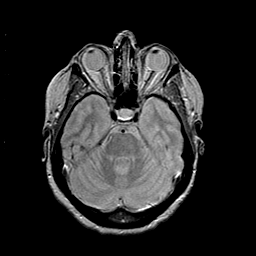

MR Study #2 -- Slice #18